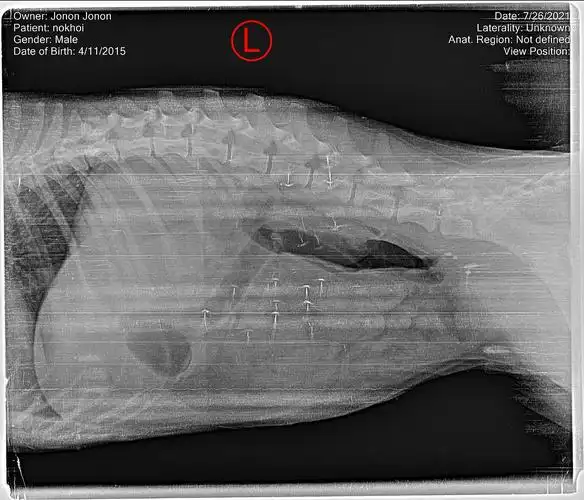

【求助】请问有会看x光片的吗?或者根据狗狗情况提供一些信息.